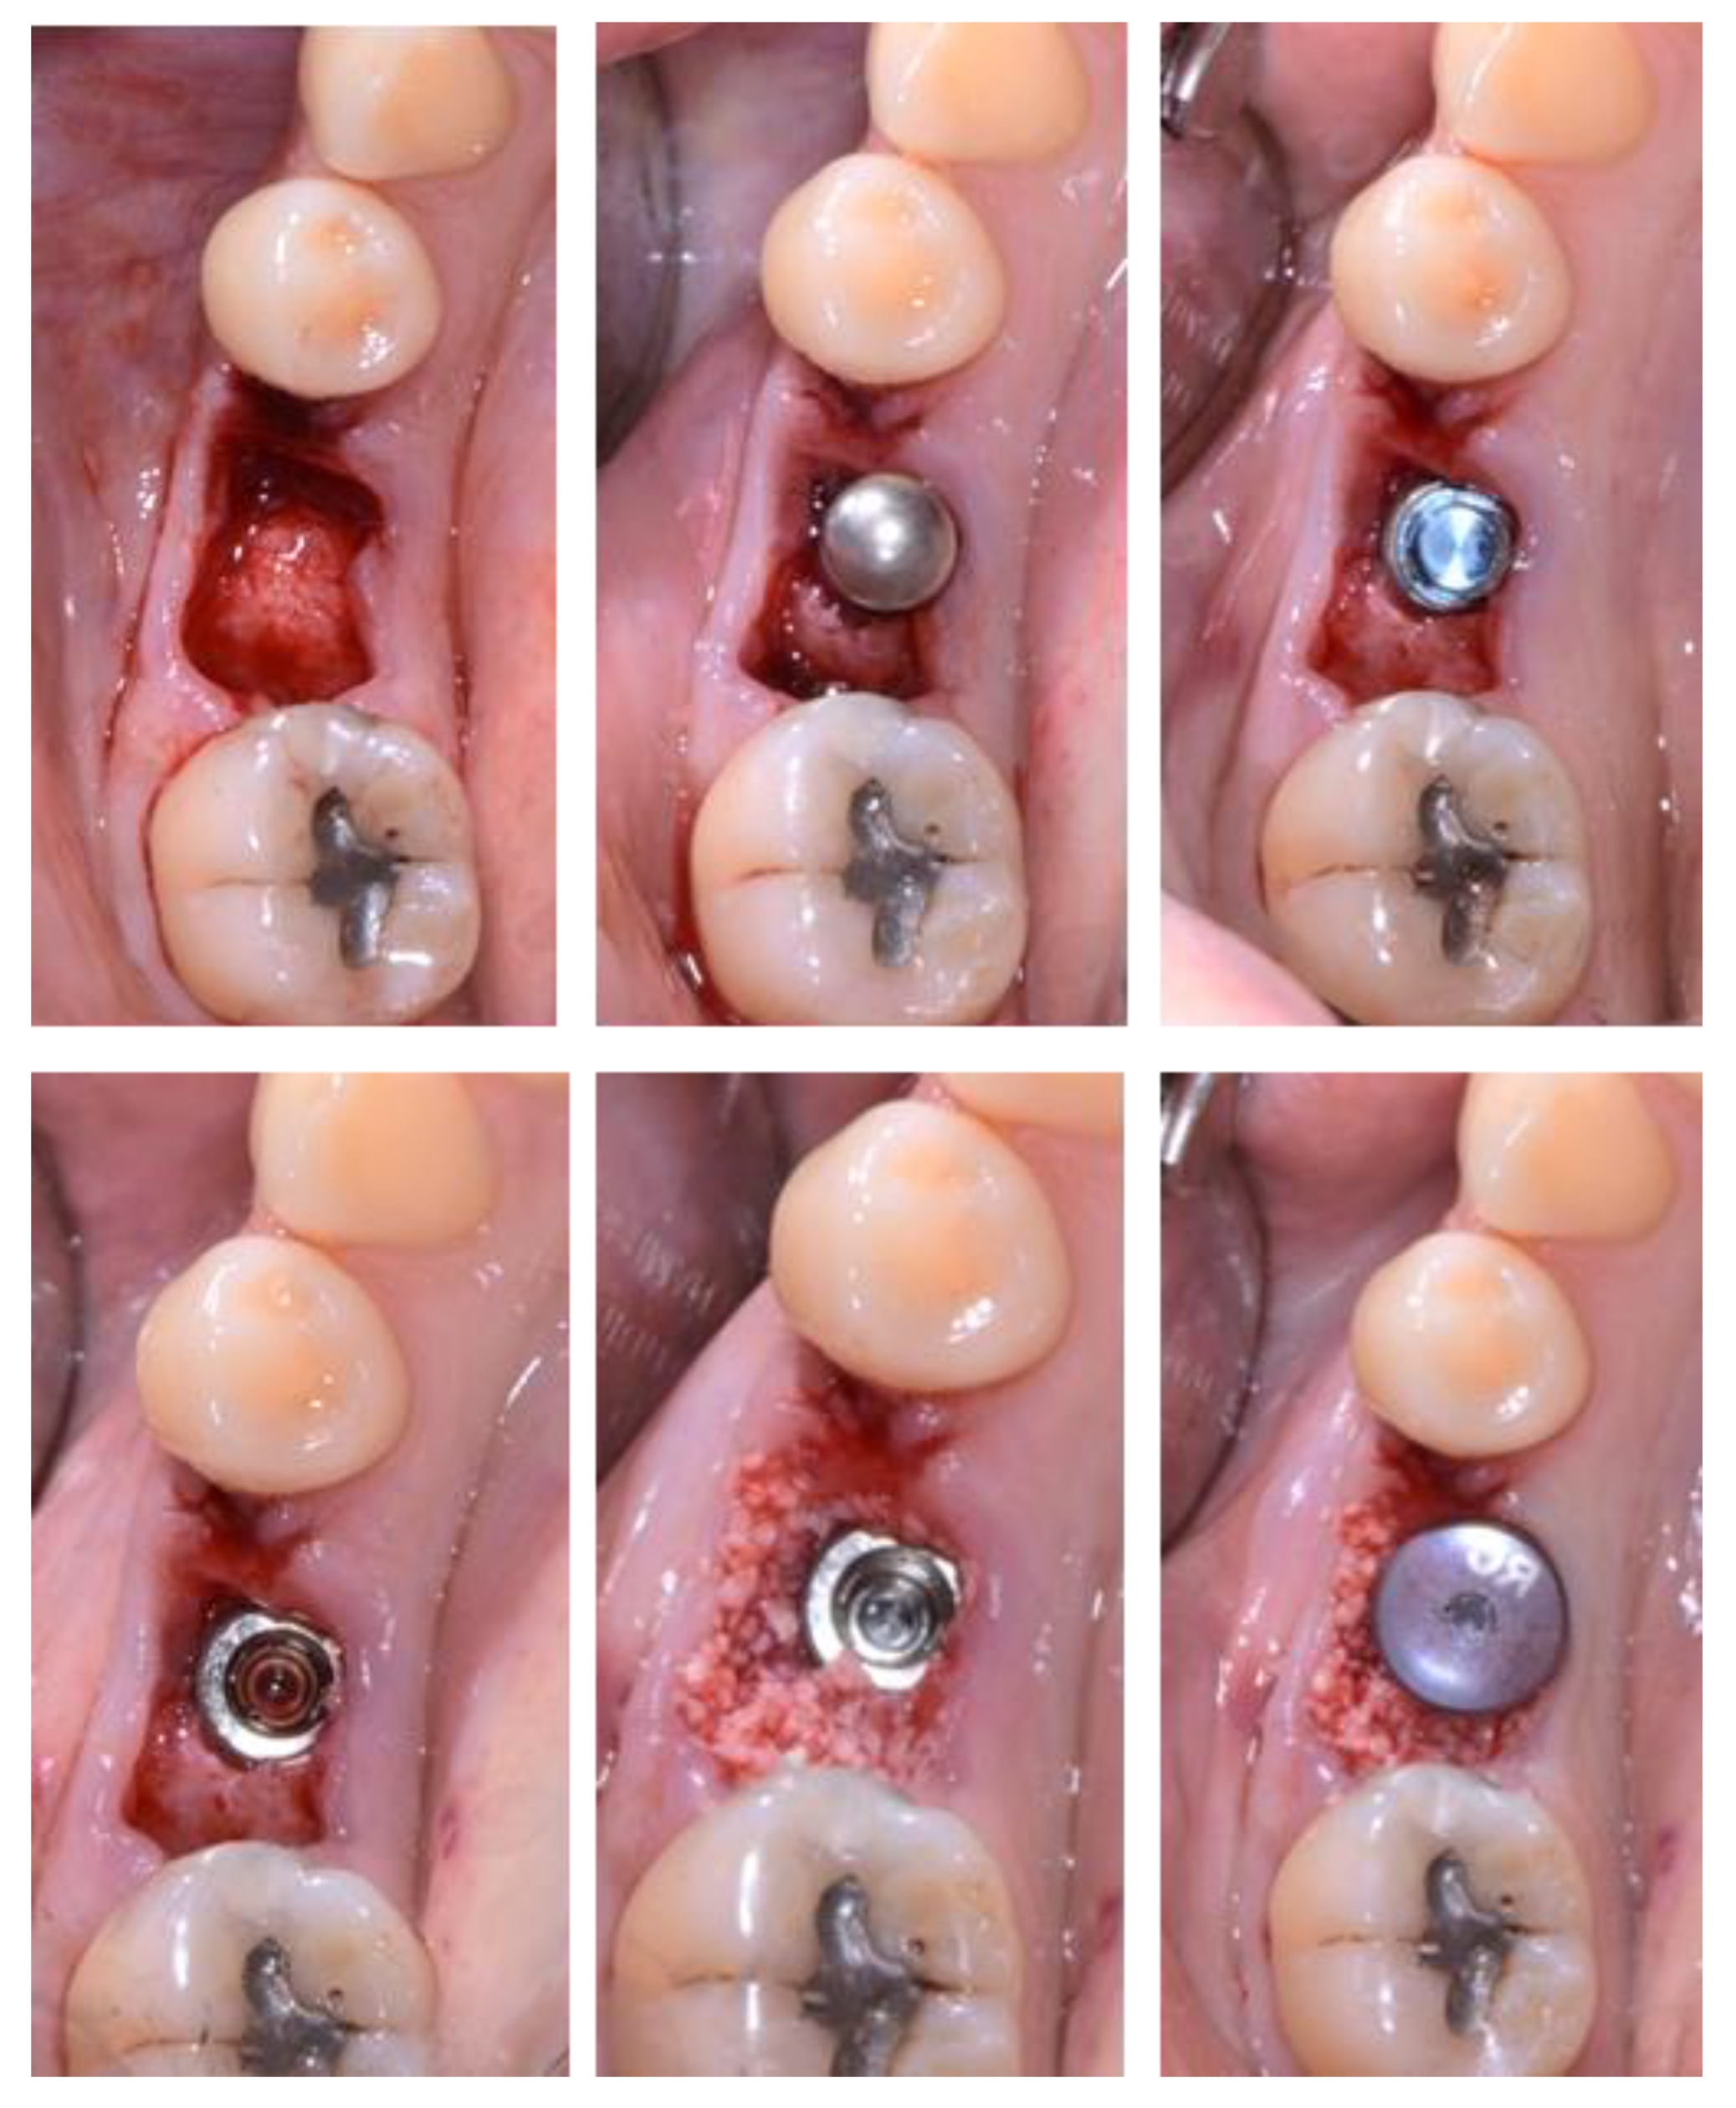

2.3. Treatment Procedure

2.5. Individual Cases Description

- Case 1:

- Case 2:

- Case 3:

- Case 4:

- Case 5: